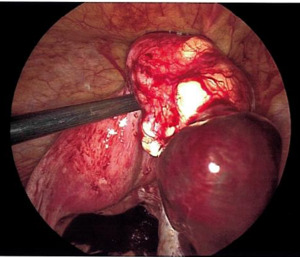

On exam, her vital signs were within normal limits. Abdominal exam revealed significant tenderness to palpation throughout the lower abdomen along with rebound tenderness. Laboratory evaluation revealed a hemoglobin of 11.9 g/dL and β human chorionic gonadotropin of 1,686 mIU/mL. Transabdominal and transvaginal ultrasound revealed a normal appearing uterus measuring 9.6 x 5.0 x 5.5 cm with no identified intrauterine gestational sac or yolk sac. There was noted to be a non-specific heterogenous, nonvascular mass of the right adnexa with no pelvic free fluid noted (Figure 1).